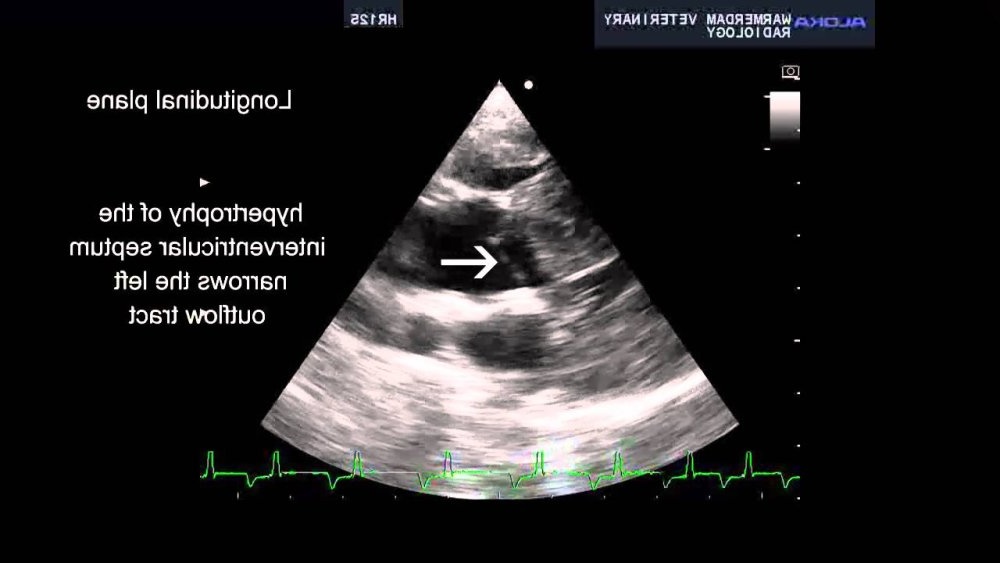

The test that matters most for HCM is an echocardiogram (ultrasound of the heart). It allows measurement of wall thickness, chamber sizes, filling patterns, and assessment for dynamic outflow obstruction or valve leakage. In many cases, your vet may recommend referral to a veterinary cardiologist, because subtle distinctions in cardiac ultrasound interpretation can change what “thickening” means clinically.1, 8

These are not “extra for the sake of it”. They help separate primary cardiomyopathy from other causes of thickened walls, and they help stage risk, which is what guides treatment decisions.1, 8